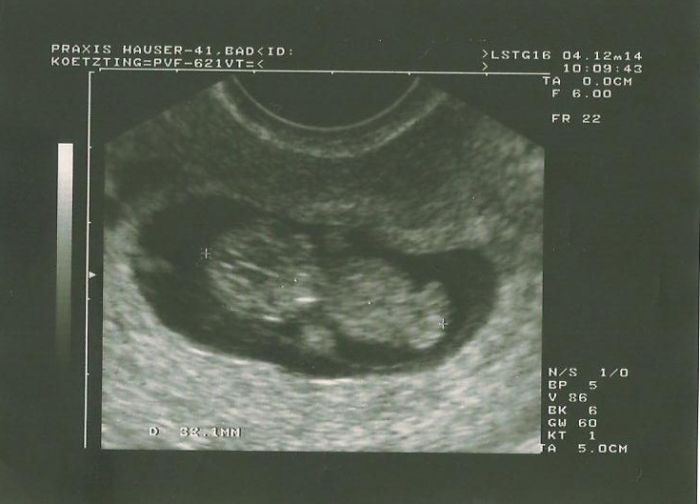

dnes 10+0 máme 3,2cm.. Vše je jak má být..

Doktor mne velice překvapil!! Cituji: Troufnu si říci, s malinkou rezervou, že tam vidím pinďoura!!!!

Jsem šťastňoučká!!!

Noo Mari0112 super, tak to je dr machr,kdyz uz to vidi takhle brzo

, velika gratulace ...

[673830] No jsem zvědavá, co se nakonec vyklube..Zírala jsem na něj, no malinká rezerva..

Uvidíme...